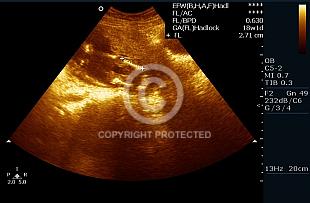

Femur Length

Standard views

882 views